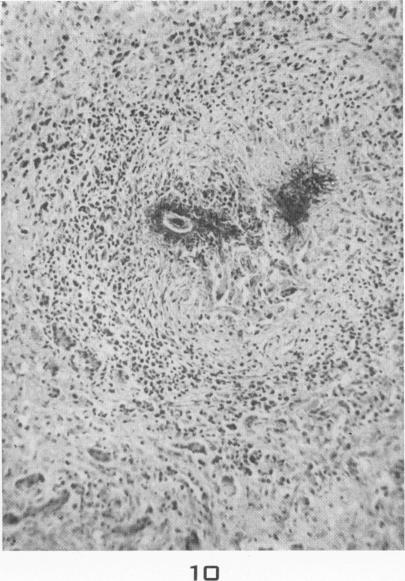

Visceral larva migrans; with a case report.

Am J Pathol. 1956 Jul-Aug;32(4):777-803.